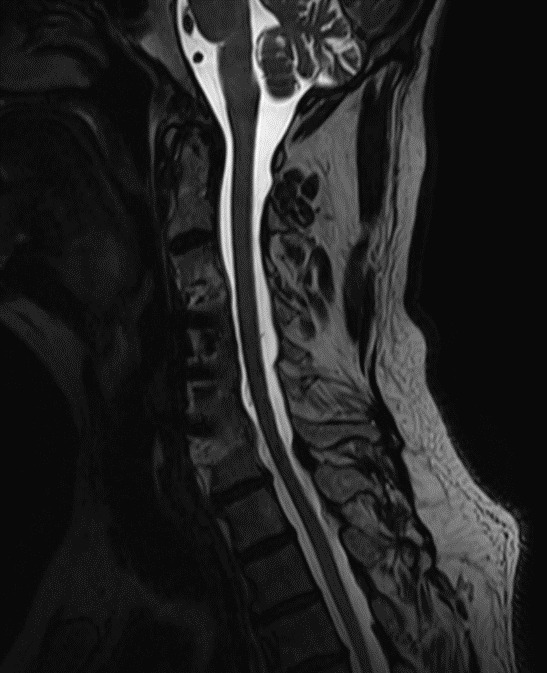

MRI (see figures 1 and 2) revealed moderate diffuse degenerative disc disease without canal stenosis with overlapping facet arthritis with associated neural foraminal stenosis. Patient presented overall neurologically intact without any neural tension signs present on exam. He did note some numbness and tingling into the right upper and lower extremities, active lumbar range of motion was limited into flexion and was provocative to LBP. Orthopedic testing revealed seated Kemp’s Test with facet loading was provocative for right-sided low back pain, while manual SI compression was unremarkable. Yeoman’s with shearing of the sacroiliac joints was unremarkable.